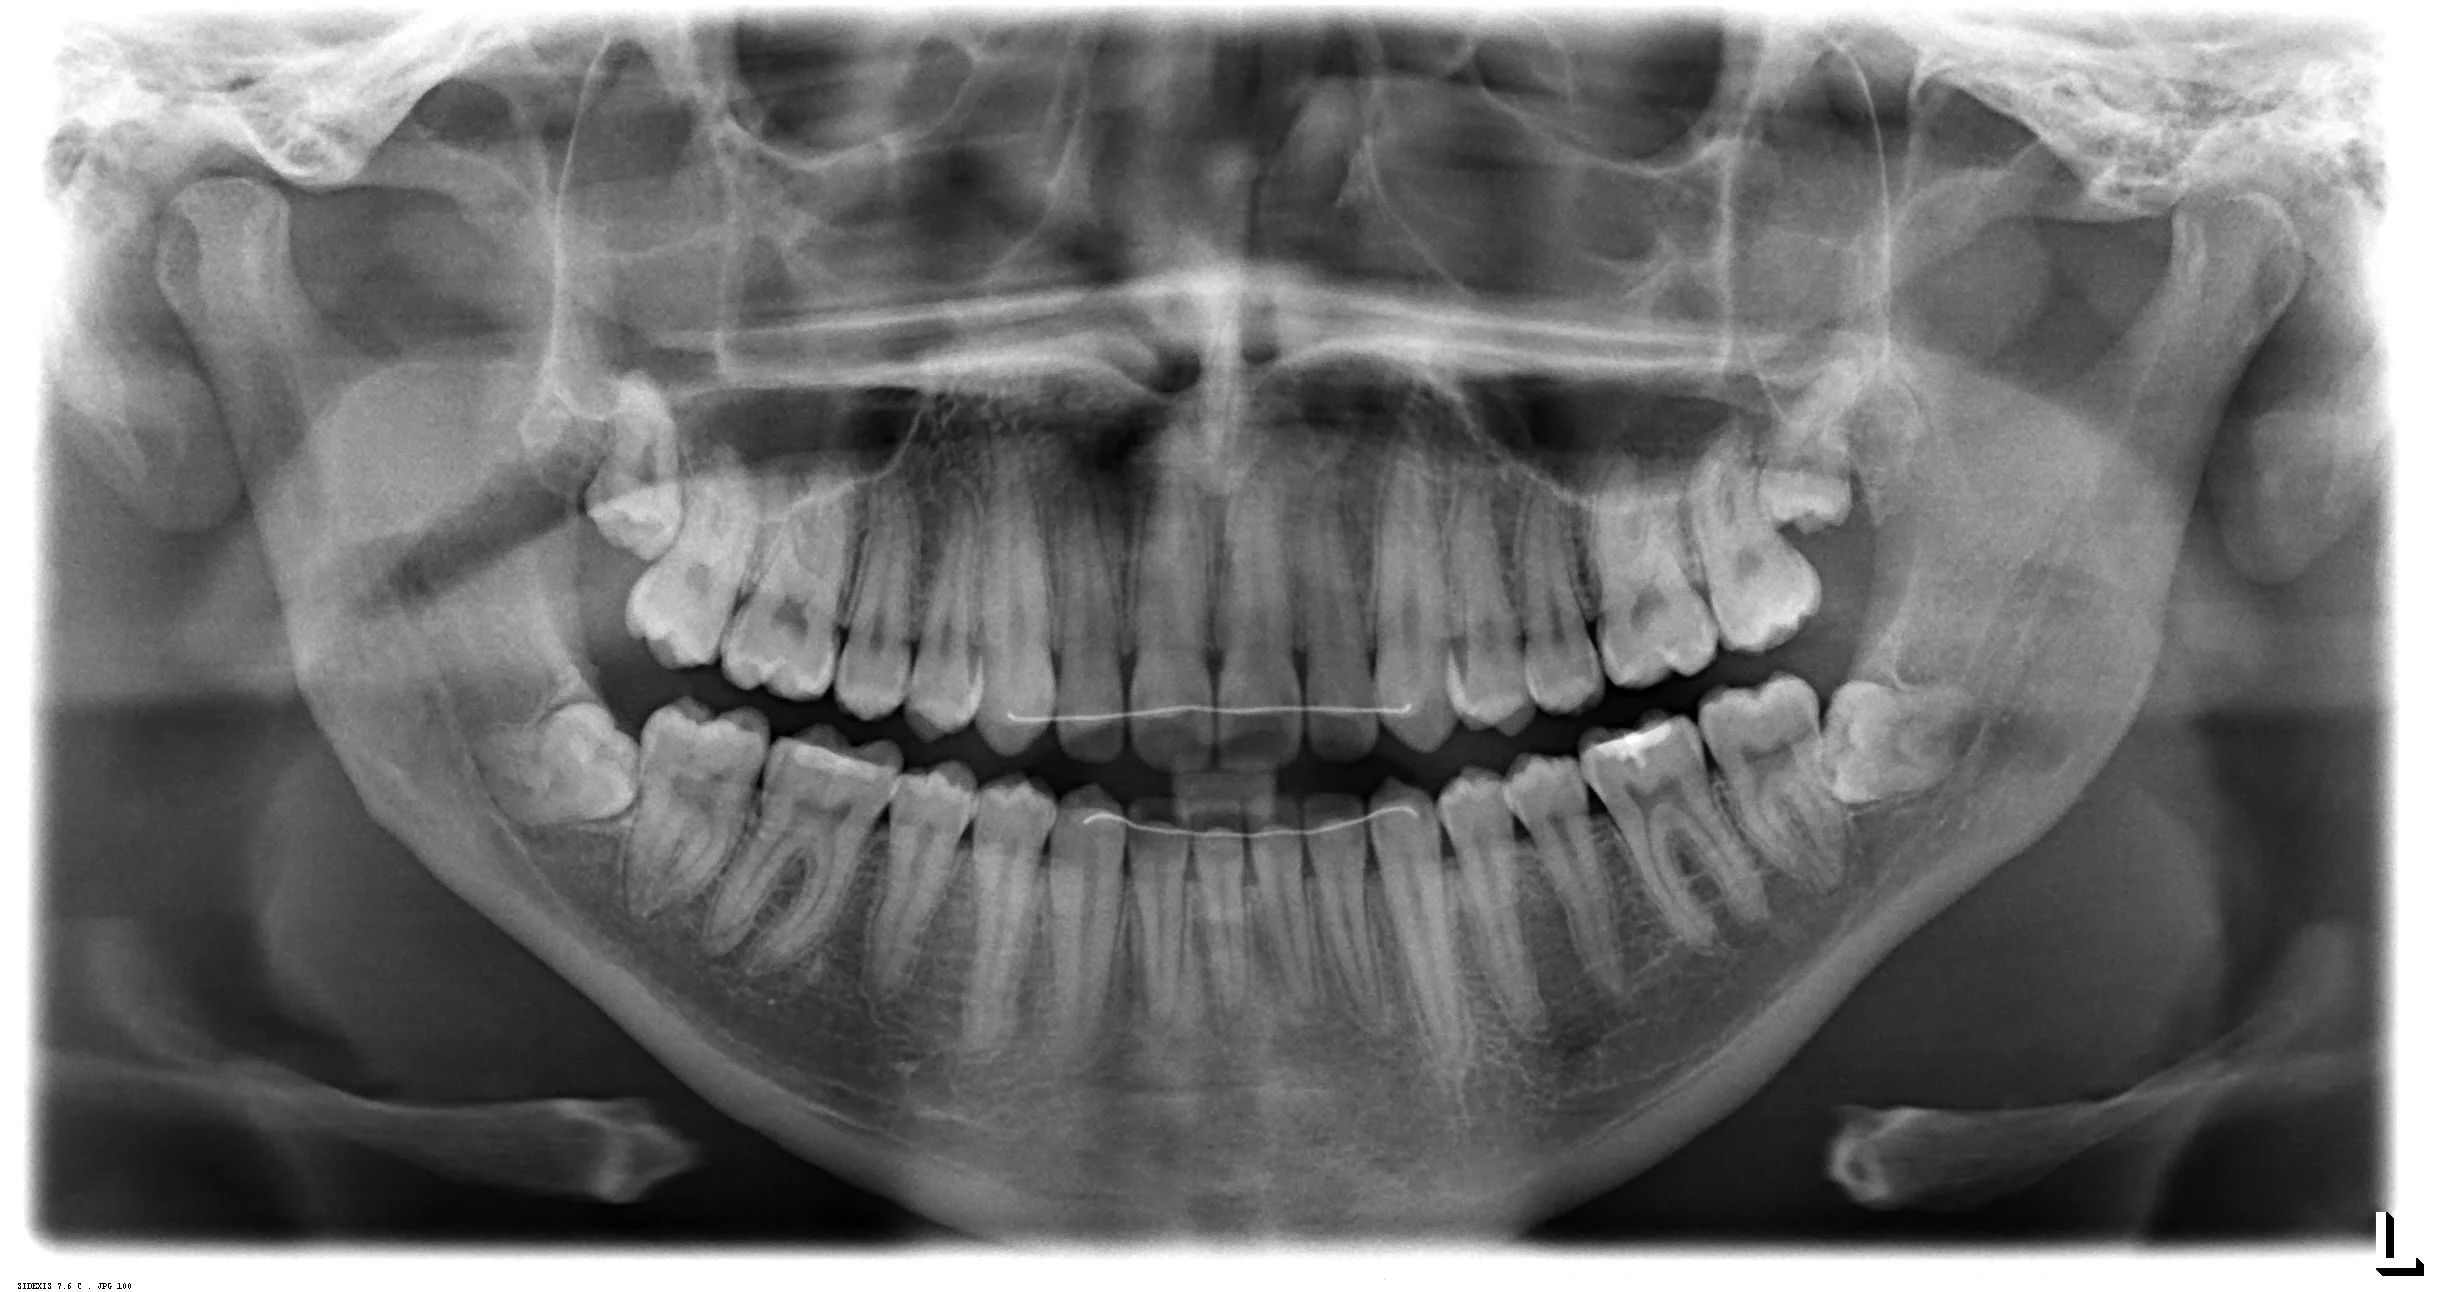

Il sera important que dans votre sélection de patient, vous nous transmettez toutes les infos par courriel (radios, cas cliniques, histoire médicale). Que vous avisiez vos patients qu’ils devront se mettre disponibles pour ces deux dates-là et que lorsque les inscriptions seront fermées, nous ferons la cédule des chirurgies.